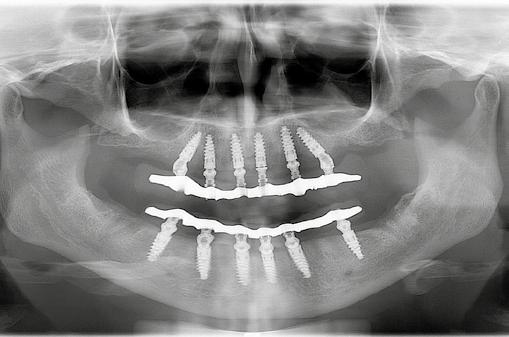

A fogak beültetéssel történő pótlása történetében – a kezdet leges megoldásokkal való korai próbálkozásokat követően –az 1950-es években történt jelentősebb változás a különböző ötvözetekből készült, subperiosteális megoldások megjelené sével és elterjedésével� Ez az első periódus két évtizeden át tartott, és egyre szélesedő alkalmazást eredményezett Majd hirtelen változott a tendencia, amikor a második korszakban, az 1960-as években, megjelentek a Linkow iskola titánból ké szült, penge típusú implantátumai, melyek szintén két évtize den át – szinte kizárólagossá válva – az 1980-as évekig ural ták a fogászati implantológiát� A Brånemark nevéhez fűződő iskola a titánból készült, és a fogak gyökeréhez hasonló for mátumú implantátumok bevezetésével hozta a harmadik korszakot Az osszeointegráció elméletének tudományos ala pokra helyezésével és a beültetés új módszertanának beve zetésével az 1980-as évektől átvette először a vezető, majd a kizárólagos szerepet Ennek a módszernek a négy évtizedes, folyamatos fejlődése eredményezte újabb és újabb tendenciák megjelenését, és hozott alapvető változásokat a gyakorlatban 2011-re világ szerte elfogadottá váltak a modern fogászati implantológia legfontosabb alapelvei, indikációs köre, anyagtana, műtét technikája, protetikája, protokolljai Implantológiai iskolák jöt tek létre, bevonult új, önálló szakterületként a sztomatológia tudományágai közé, egyetemi oktatási tantárggyá vált, és ma már szakorvosi képesítést is lehet szerezni orális implanto lógiából Ismeretanyaga önállóan, valamint a tradicionális fogászati tárgyak – parodontológia, szájsebészet, protetika –tudományos ismeretanyagát és módszereit magába foglalva, folyamatosan gyarapodik, és a fogászat legdinamikusabban fejlődő ágazata lett Az egész világon napjainkra a fogászati implantológia önálló disciplinává vált A fejlődés rendkívül dinamikus, a tudásanyag egyre hatalma sabbá nő� Számos területen – már evidenciák alakultak ki, me lyekre szakmai protokollok épülnek – olyan folyamatos válto zásokat figyelhetünk meg, hogy ezek már nehezen követhe tők Jelen munkánk célja a gyakorlatban megjelenő változások közötti eligazodás, valamint az egyes fontosabb fejlődési ten denciák áttekintése (1–2. ábrák) Fontos tendenciákat mutatnak a Lancetben megjelent adatok� A 10 évet meghaladó megfigyelések szerint az implantátumok túlélése meghaladja a 90%-ot� Jelentős az idős lakosság ará nyának a növekedése, Európa lakosságának több mint 20%-a, az USA lakosságának több mint 30%-a lesz 65 év feletti 2030ra Évtizedes tapasztalatok azt mutatják, hogy 65 év felett is sikeresen végezhetőek az implantológiai beavatkozások Idős korban azonban gyakoribbak a krónikus betegségek, melyek miatt az idősek implantáció előtti kivizsgálása és utókezelése több időt és odafigyelést igényel

Gáspár Máté A FOGÁSZATI IMPLANTOLÓGIA FEJLŐDÉSI TENDENCIÁI Változások a gyakorlatban 1. ábra: Cortilog short 3,8–6 mm implantátum egyenes fejjel, platform switch kialakítással. 2. ábra: Straumann implantátumok egyes típusai